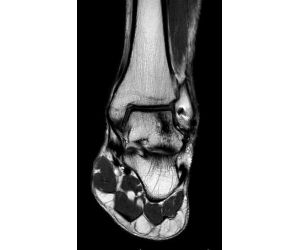

Progressive collapsing foot deformity with tibiotalar arthritis… a challenging problem

Jordan Sisto, DPM, FACFAS

Here we have a 69 y/o male with staged TAA on right that led to AVN talus and collapse which ultimately was revised to TTTA with great success -...